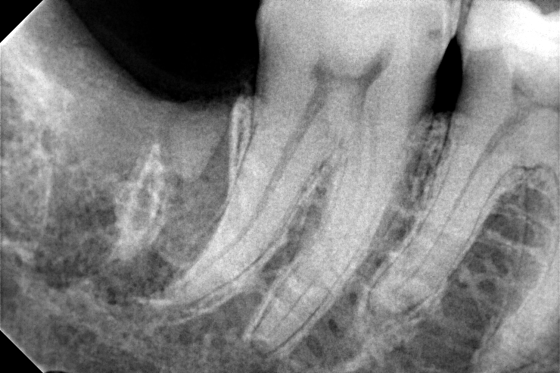

Στην περίπτωση που ο φρονιμίτης παρουσιάζει περιοδικά ή συστηματικά συμπτώματα πόνου στον ασθενή συστήνεται η αφαίρεσή του. Η εξαγωγή φρονιμίτη σε μεγάλο ποσοστό δεν είναι μία εύκολη εξαγωγή. Ο οδοντίατρος πολλές φορές θα πρέπει να αφαιρέσει κόκκαλο ή να σχίσει το ούλο για την ομαλή απομάκρυνση του δοντιού από το στόμα χωρίς να σπάσει η ρίζα ή να μείνει κάποιο υπόλειμμα του δοντιού στη γνάθο.

Η εξαγωγή φρονιμίτη απαιτεί εμπειρία και την κατάλληλη υλικοτεχνική υποστήριξη του οδοντιάτρου για την ομαλή απομάκρυνση του δοντιού από το στόμα χωρίς επιπλοκές και πόνο.